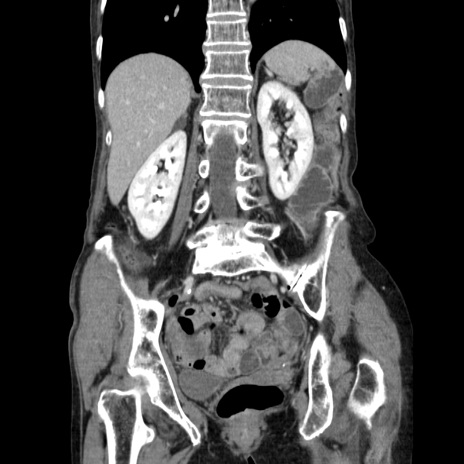

症例25(冠状断像)

【症例】80歳代女性

【主訴】胸のつかえ感

【現病歴】約9時間前に食後から胸のつかえた感じあり、嘔吐あり、来院。

【既往歴】胃癌(全摘)、胆摘、虫垂炎

【身体所見】心窩部に圧痛あり、反跳痛なし。

【データ】WBC 5700、CRP 0.05